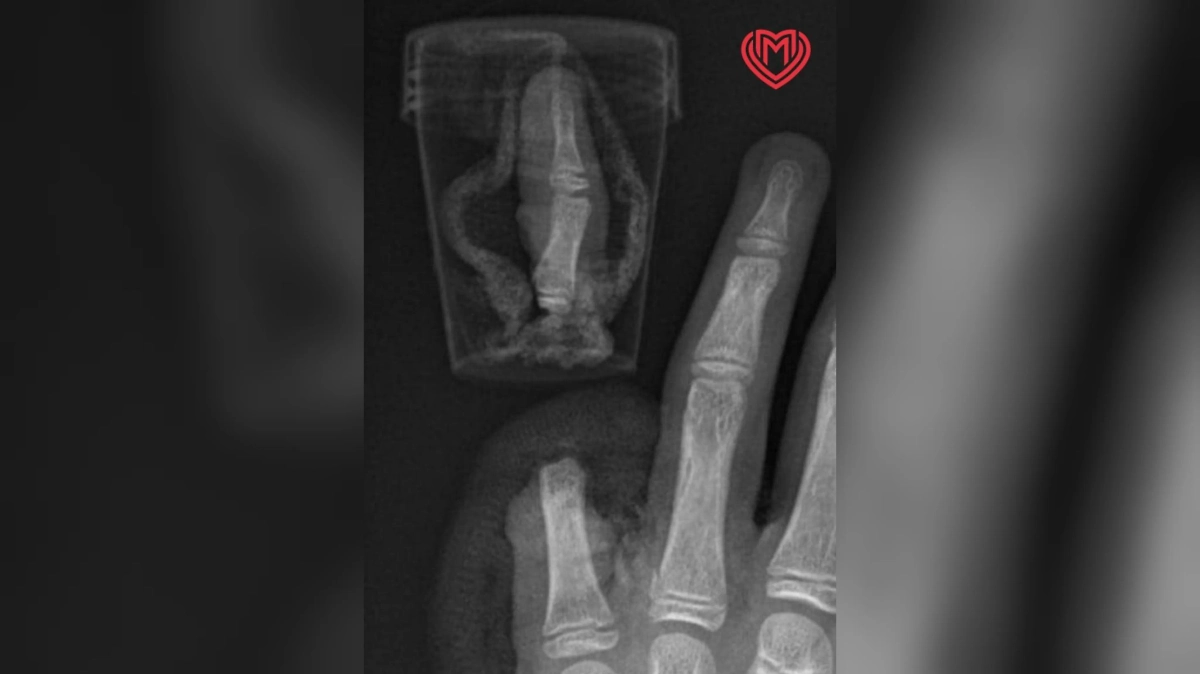

В Москве 12-летний мальчик решил порадовать родителей, приготовив им чай в настоящем самоваре, однако во время колки дров по неосторожности отрубил себе палец. Пострадавшего госпитализировали в столичную больницу, где хирурги провели успешную операцию. Об этом сообщается в телеграм-канале «Московская медицина».

В столичной больнице пострадавшему постепенно соединили кости, сухожилия, а также сгибатели и разгибатели пальца. Наиболее сложным оказался микрохирургический этап операции, во время которого мальчику сшивали нервы и сосуды. Трудоёмкий процесс завершился успехом, в дальнейшем палец подростка будет срастаться как обыкновенный перелом. Максима выписали и отправили домой, врачи дают положительный прогноз касательно реабилитации.